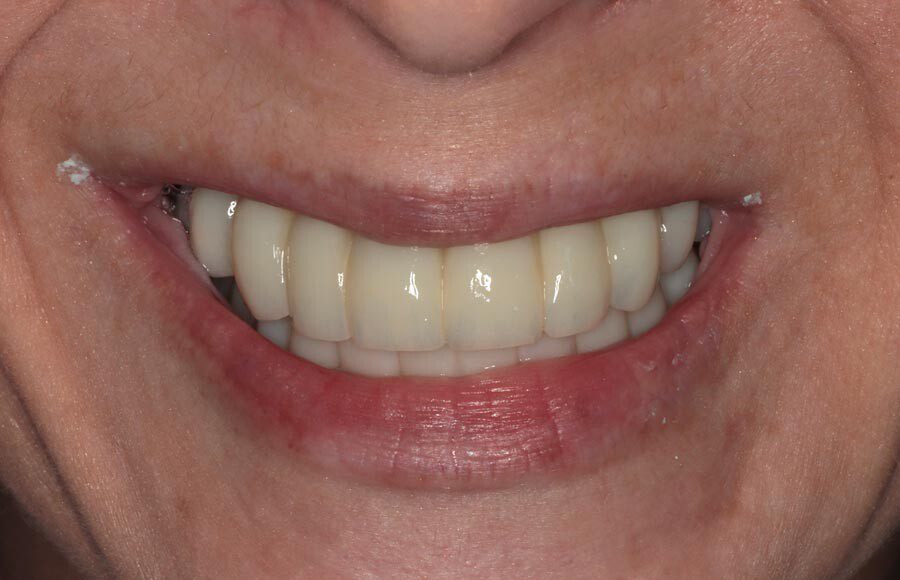

The definitive bridges are delivered, the bite is verified, and the screws are torqued down firmly. The final result is strong, functional, and esthetic restorations that will serve the patient well for years to come.

The patient couldn’t be happier with her new smile. We have improved not only her esthetics but her oral health as well. She now has beautiful restorations she can keep for years to come. Contact us if you would like to have a consultation and see if this is the right treatment for you!